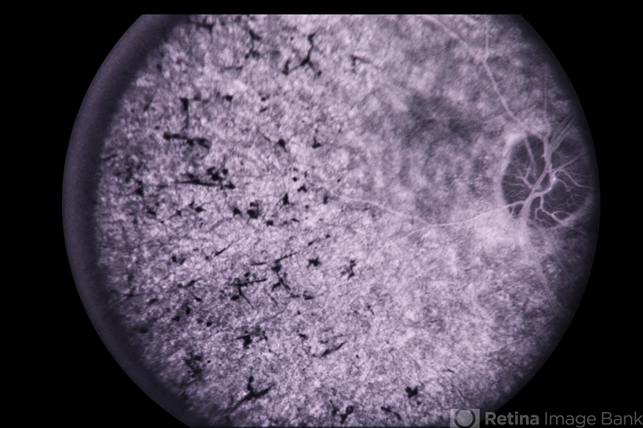

systemic lupus erythematosus (SLE) retinopathy

44-year-old female, SLE - systemic lupus erythematosus; treated for 2 years with 250 mg chloroquine BID.